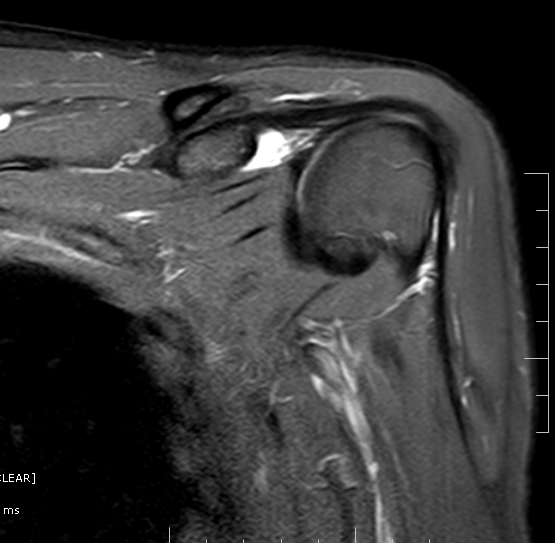

SubcoracoidSubscapularis Bursa MRI Sumer's Radiology Blog Scapular Bursitis Mri Web mri in snapping scapula syndrome, which is a clinical diagnosis, exquisitely reveals soft tissue changes. Finally, an mri can be used to. Web scapulothoracic bursae refer to a number of bursae that allow for the gliding movement of the scapulothoracic joint. Web they discovered bony incongruity in 26 of 26 scapulae. Web more recently, mri and ultrasound have been. Scapular Bursitis Mri.

SubcoracoidSubscapularis Bursa MRI Sumer's Radiology Blog Scapular Bursitis Mri Web scapulothoracic bursitis refers to inflammation of the bursae secondary to trauma or overuse owing to sports. Web they discovered bony incongruity in 26 of 26 scapulae. Web mri in snapping scapula syndrome, which is a clinical diagnosis, exquisitely reveals soft tissue changes. Web the initial treatment of scapulothoracic bursitis and scapulothoracic crepitus should be nonoperative. Web scapulothoracic bursae refer. Scapular Bursitis Mri.